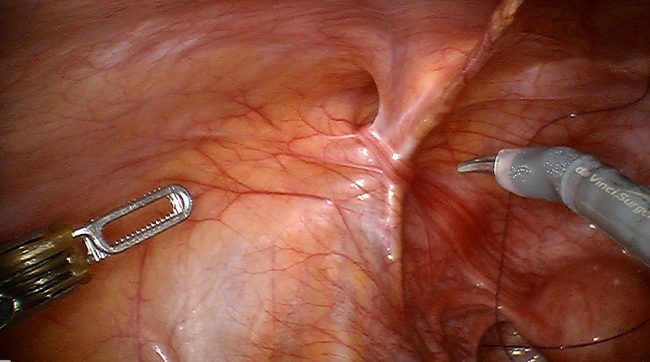

Robotic assisted repair of recurrent right inguinal hernia with mesh

This is a 52 year old male with history of right inguinal hernia repair 10 years ago who presented with a painful bulge in the right groin. Patient underwent a robotic assisted repair of recurrent right inguinal hernia with mesh. There was an evidence of recurrent right inguinal hernia on the most medial aspect of the pervious hernia repair with incarcerated pre-peritoneal fat in the hernia defect.